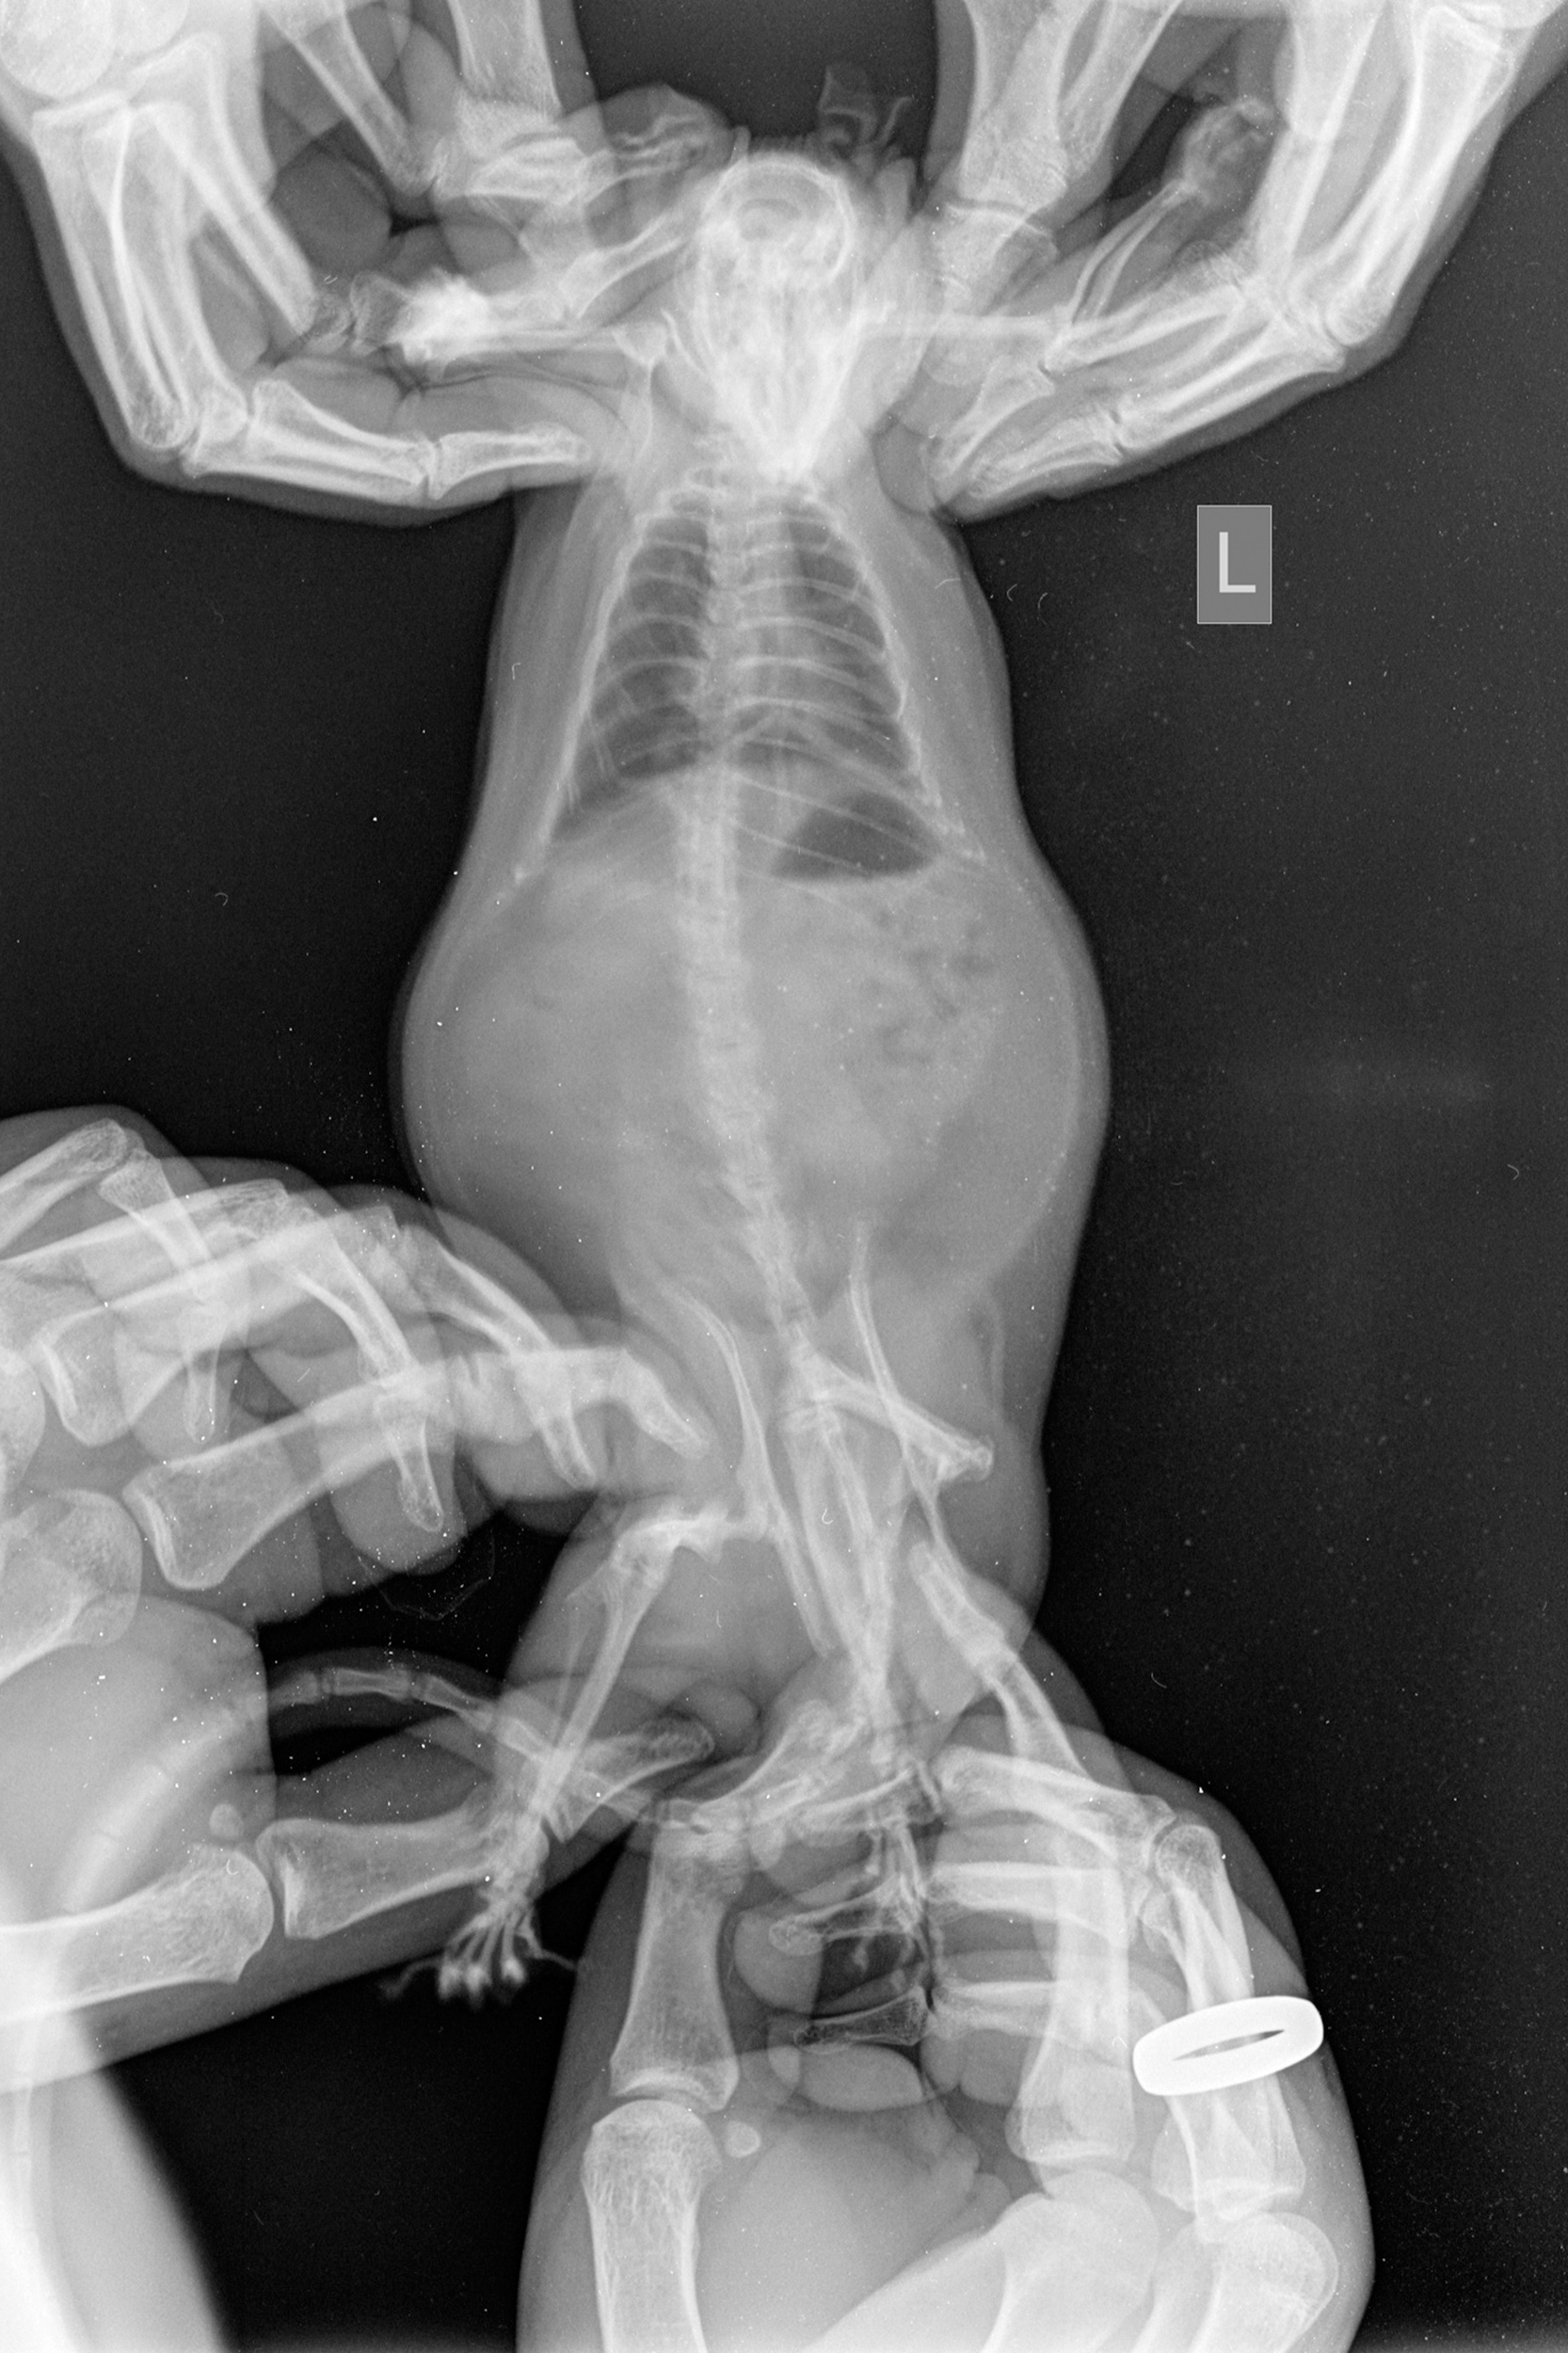

AS: The second book is dedicated to Maryia Karneyenka’s visual project Rattus Sapiens. It emerged from her activism and personal experience of interacting with rats — relationships that go beyond the concept of “ownership,” because they are not defined or limited by possession. For the project, Maryia uses not only photography but also creates collages, still lifes, and gives new meanings through appropriation in order to show what lies behind stigma. In this case, however, the publication was constructed as a two-voice dialogue of visual and textual parts. On the one hand, Maryia’s visual project Rattus Sapiens, and on the other, the textual voice of Tatsiana Zamirovskaya.

Art book Rattus Sapiens by Maryia Karneyenka / subject photos of the publication by Maryia Karneyenka / photo provided by the publisher.

Photo from the Rattus Sapiens project by Maryia Karneyenka / image provided by the publisher.